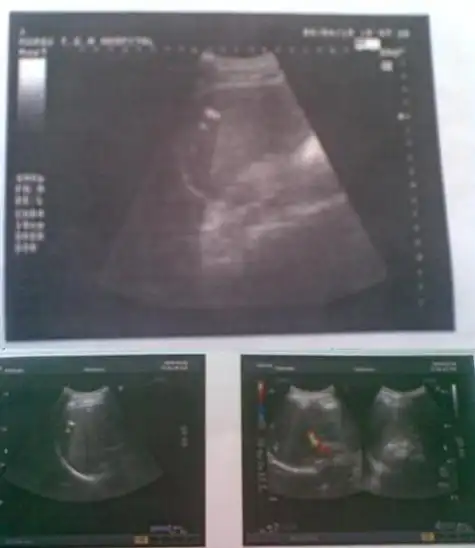

多发性结石

肿大的胆囊张力很高,胆囊壁增厚,囊内胆汁透声不佳,有结石,有胆泥沉积